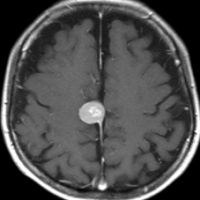

- 下のMRIは66歳の女性に脳ドックで偶然見つかった髄膜腫です.左の写真は1995年,右は2005年です。10年間で全く大きくなっていません